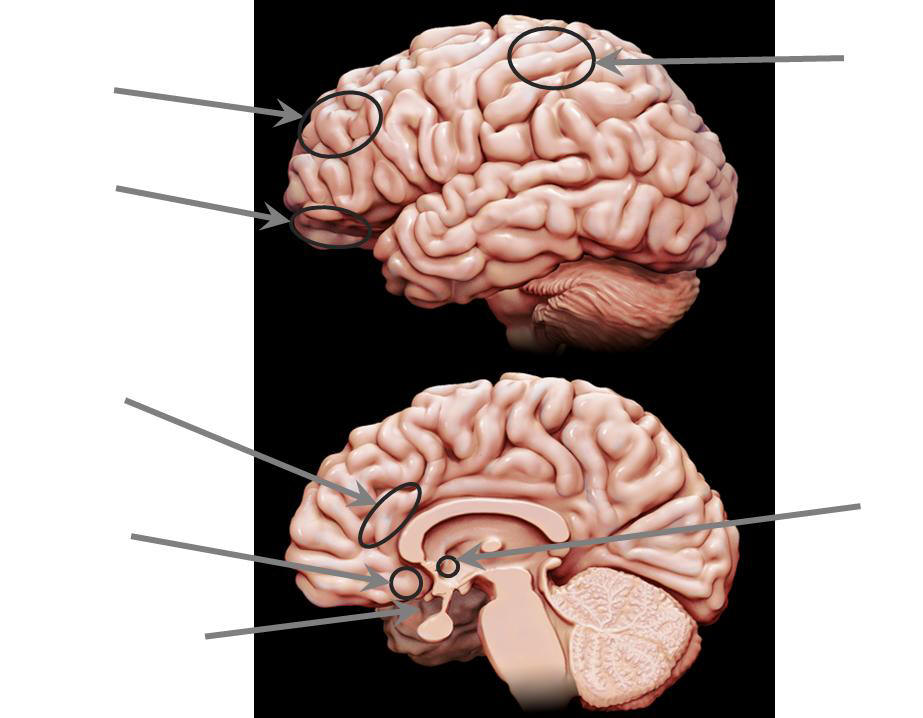

1.1 Eine kleine Gehirn-Anatomie und Arbeitsteilung im Gehirn: Unsere vier „Minigehirne“

Die vier Hirnregionen des „klassischen“ (links) und aktualisiert erweiterten (oben) Lust-, Belohnungs- und Glückssystems

Vielmehr tragen mindestens sieben Hirnregionen zum Entstehen, biochemischen Aufbau und Erleben unseres Glücks bei, wobei noch zwei weitere zu seinem jeden erkennbaren motorisch-muskulären Gesichtsausdruck hinzukommen können.

Vorweg muss allerdings betont und darauf hingewiesen werden, dass diese Hirnregionen eng miteinander verwachsen sind vorwärts und rückwärts miteinander kommunizieren und keine Hirnregion der alleinige Ort unseres Glücks und Wohlbefindens ist. Glücksgefühle sind – wie alle Emotionen, Gefühle und Stimmungen ein elektro-biochemisch neurobiologischer Lebensprozess, der sich räumlich und zeitlich aufbaut und entfaltet.

Am Aufbau unserer freudigen Erwartungen, Vorfreude, inneren Antriebs (Motivation), Freude, „allem was uns gut tut“ und Glücksgefühle (sowie allen legalen Genussmitteln, allen Verhaltenssüchten wie die zur Zeit topaktuelle Spielsucht und allen illegalen Drogen und Süchten) sind also beteiligt: